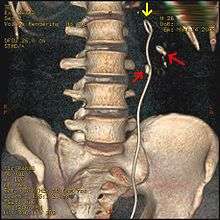

Otherwise a noncontrast helical CT scan with 5 millimeters (0.2 in) sections is the diagnostic modality of choice in the radiographic evaluation of suspected nephrolithiasis.[12][42][45][46][3] All stones are detectable on CT scans except very rare stones composed of certain drug residues in the urine,[47] such as from indinavir. Calcium-containing stones are relatively radiodense, and they can often be detected by a traditional radiograph of the abdomen that includes the kidneys, ureters, and bladder (KUB film).[47] Some 60% of all renal stones are radiopaque.[45][48] In general, calcium phosphate stones have the greatest density, followed by calcium oxalate and magnesium ammonium phosphate stones. Cystine calculi are only faintly radiodense, while uric acid stones are usually entirely radiolucent.[49]

Ureteroscopy has become increasingly popular as flexible and rigid fiberoptic ureteroscopes have become smaller. One ureteroscopic technique involves the placement of a ureteral stent (a small tube extending from the bladder, up the ureter and into the kidney) to provide immediate relief of an obstructed kidney. Stent placement can be useful for saving a kidney at risk for postrenal acute renal failure due to the increased hydrostatic pressure, swelling and infection (pyelonephritis and pyonephrosis) caused by an obstructing stone. Ureteral stents vary in length from 24 to 30 cm (9.4 to 11.8 in) and most have a shape commonly referred to as a "double-J" or "double pigtail", because of the curl at both ends. They are designed to allow urine to flow past an obstruction in the ureter. They may be retained in the ureter for days to weeks as infections resolve and as stones are dissolved or fragmented by ESWL or by some other treatment. The stents dilate the ureters, which can facilitate instrumentation, and they also provide a clear landmark to aid in the visualization of the ureters and any associated stones on radiographic examinations. The presence of indwelling ureteral stents may cause minimal to moderate discomfort, frequency or urgency incontinence, and infection, which in general resolves on removal. Most ureteral stents can be removed cystoscopically during an office visit under topical anesthesia after resolution of the urolithiasis.[93]